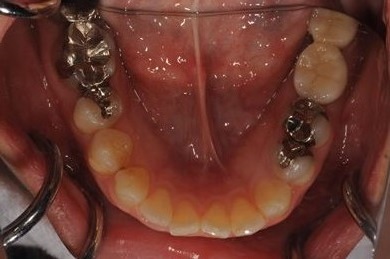

抜歯即日スピードインプラント治療+セラミック治療+歯肉歯槽骨整形術

| 治療方針 | 左下欠損部と保存不能の歯を抜歯し、インプラント治療にて機能的・審美的回復を行う。 | ||||||||||||||||||||||||||||||||

| 治療内容 | インプラント2本(抜歯即日スピードインプラント)、ハイブリッドセラミッククラウン2本、歯肉歯槽骨整形術 | ||||||||||||||||||||||||||||||||